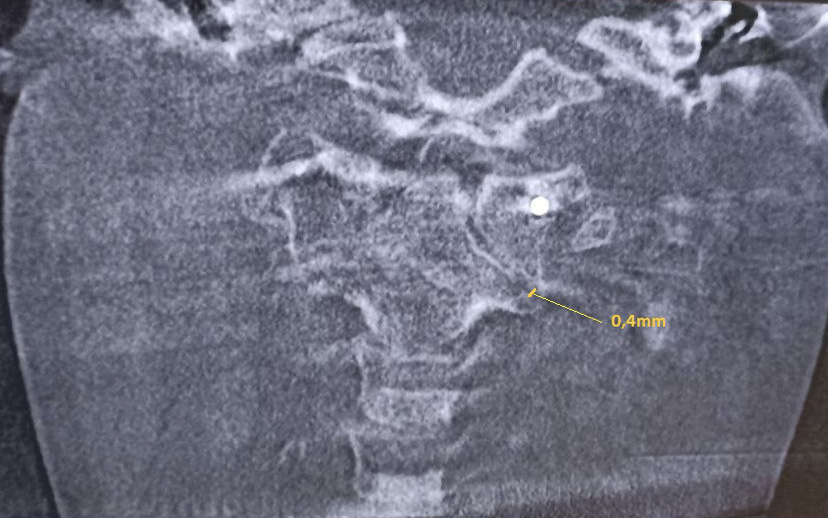

Для оценки ситуации в динамике была проведена КЛКТ, на которой на фоне динамической нерезкости (ребенок был неусидчив) и артефактов от металлоконструкции было отмечено следующее: суставные рентгеновские щели в латеральных атлантоаксиальных суставах: справа – не прослеживается, слева – неравномерно сужена до 0,4 мм в наиболее узком месте (рис. 6). Рентгеновская щель срединного атлантоаксиального сустава в сагиттальной плоскости не прослеживается (рис. 7А), в парасагиттальной плоскости – прослеживается, неравномерная (рис. 7Б). Зубовидный отросток С2 позвонка визуализируется в виде 2 фрагментов, дистальный из которых вместе с передней дужкой С1 позвонка представлен в виде не полностью слитного костного образования. Проксимальный фрагмент, лоцирующийся в проекции верхушки зубовидного отростка С2 позвонка, представлен в виде свободно лежащего отломка с неравномерно склерозированным контуром в проекции диастаза (см. рис. 7). Данная рентгенологическая картина соответствует состоянию после оперативного лечения по поводу травмы шейного отдела позвоночника со стабилизацией металлоостеосинтезом С1–С2 позвонков. Неправильно сросшийся перелом зубовидного отростка С2 позвонка. Частичный анкилоз срединного атлантоаксиального сустава и полный анкилоз правого латерального атлантоаксиального сустава.

Рис. 6. Конусно-лучевая компьютерная томография краниовертебральной области, фронтальный срез на уровне зубовидного отростка С2 позвонка